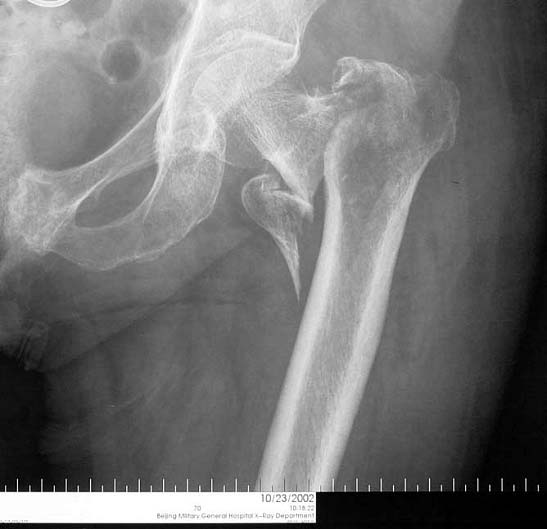

股骨粗隆间骨折,严重移位。            采用闭合复位伽马钉内固定。